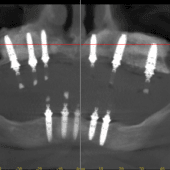

TovábbSzinte kész💥 Egy Facebook posztunkból Előtt-után ✈️ Németországból jött hölgy összes megmaradt felső fogát, valamint alul mindkét oldalon 2-2 hátsó […]